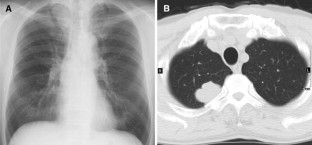

Primary pulmonary choriocarcinoma is a very rare tumor and eventually diagnosed by pulmonary resection. A poor prognosis has been reported for this disease, but appropriate treatment has not been established. Here, we report the successful surgical treatment for a primary pulmonary choriocarcinoma. A 70-year-old male presented with cough and a 3.8-cm solid tumor was detected in the right upper lobe of the lung on CT scan. Results of an open lung biopsy indicated carcinoma with indeterminate histological subtype. Right upper lobectomy was performed and the permanent pathological diagnosis was choriocarcinoma. Right after surgery, systemic and genital screening was performed by urologist, but no abnormal findings were observed. Elevation of serum β-hCG was confirmed at the same time and the value dropped within normal range in 2 months. According to diagnosis criteria, we reached final diagnosis of primary pulmonary choriocarcinoma. The patient has been alive with no recurrence for 2 years after surgery.

Fig. 1